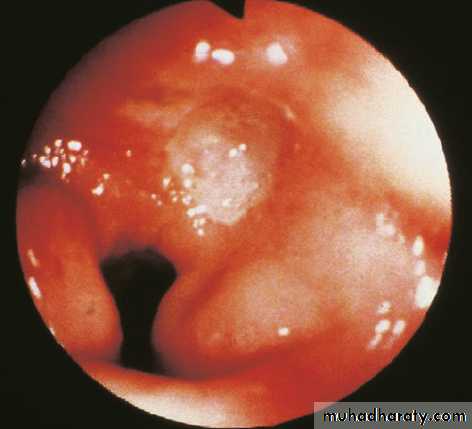

Intestinal metaplasia with dysplasia is pre malignant condition that needs regular OGD follow up.

1—INTESTINAL GASTRIC CANCER (Arise in intestinal metaplasia)

A—POLYPOIDAL.

B—ULCERATIVE

form a diffuse mucosal thickening, which may ulcerate

Diagnosis made by endoscopic biopsy.